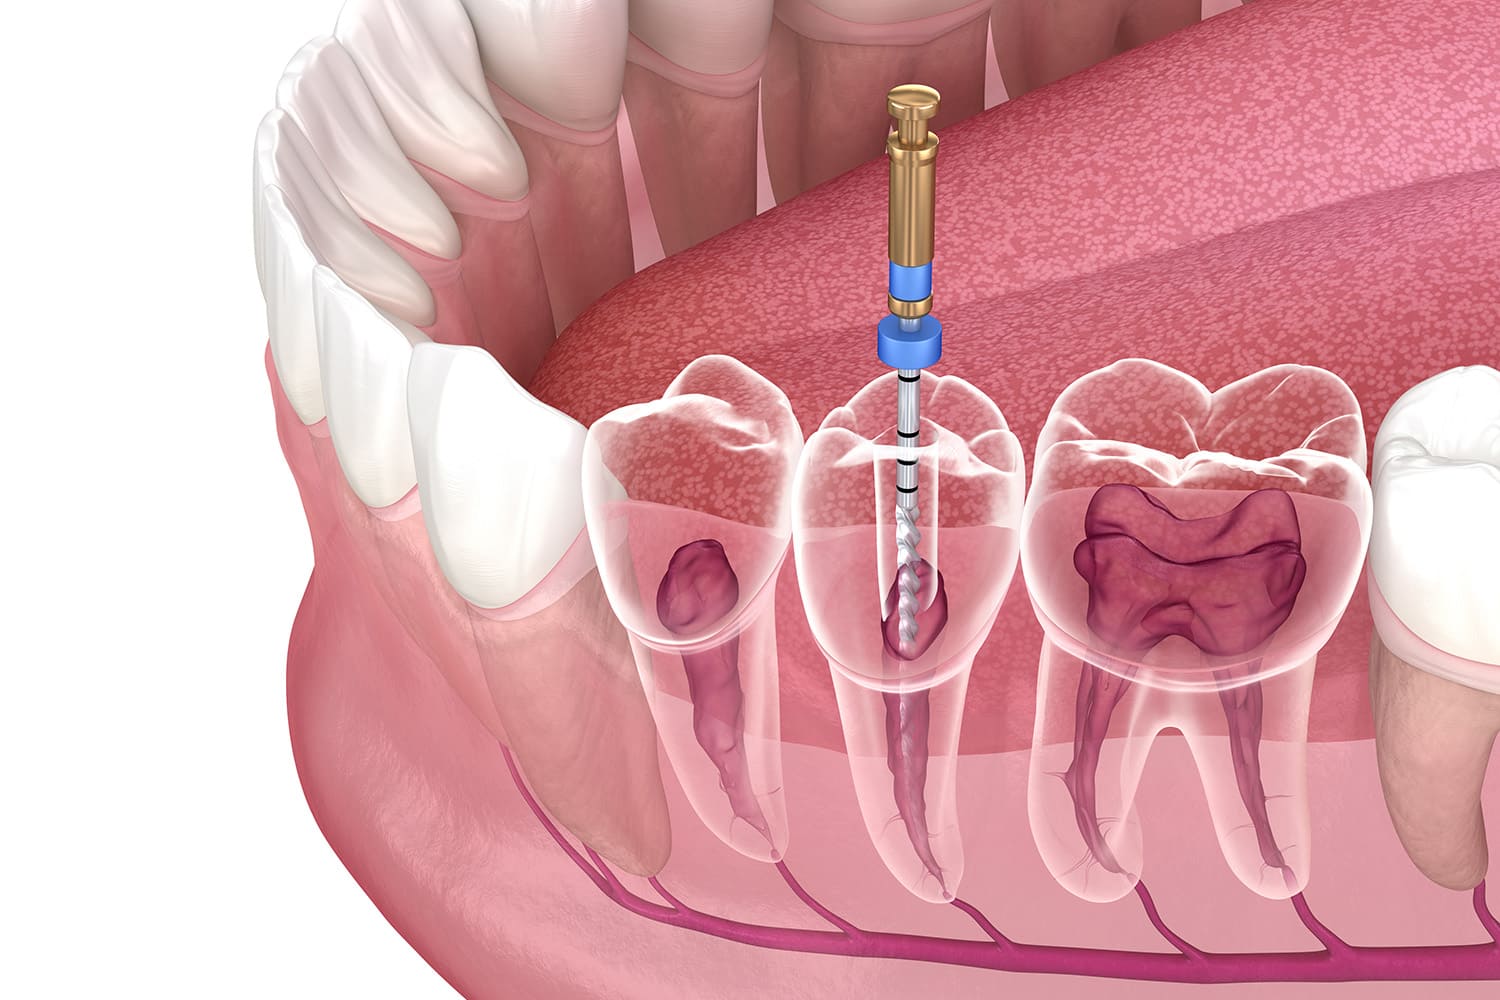

精密根管治療

根管治療とは、歯の中にある神経(歯髄)や血管が通る細い管=根管をきれいに清掃し、再び細菌が入らないように密封する治療のことをいいます。当院では、できる限り再発を防ぎ、長く自分の歯を保つために精密な治療環境を整えています。